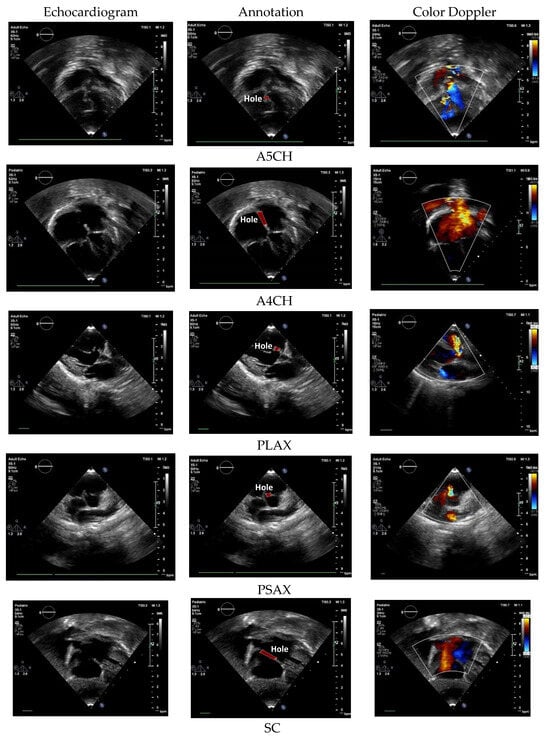

The main standard cardiac views are A4CH, A5CH, PLAX, PSAX, and SC (Figure 2) [9,10]. A4CH and A5CH in apical view are essential during hemodynamic assessment of the cardiac tissue [11]. A4CH presents the chamber walls of two atria and two ventricles. Different from A5CH, it displays the appearance of the aortic valve and the left ventricular outflow tract [9]. PLAX and PSAX allowed for the measurement of the size of the left atrium, which is used for assessing the valvular function. PSAX provides a cross-sectional view of the heart and allows for an assessment of the left ventricular function [12]. SC provides a similar visualization of the structures seen in apical A4CH, but it is viewed from a different angle [10]. In this study, we also use Doppler US video to ensure the defect condition and provide real-time visualization of blood flow dynamics within the heart. The Yolov8 backbone in this task is similar to normal–abnormal classification. However, the head architecture is increased to five nodes, indicating the class number.

Figure 2. The US standard cardiac view of A4CH, A5CH, PLAX, PSAX, and SC with color Doppler echocardiography.